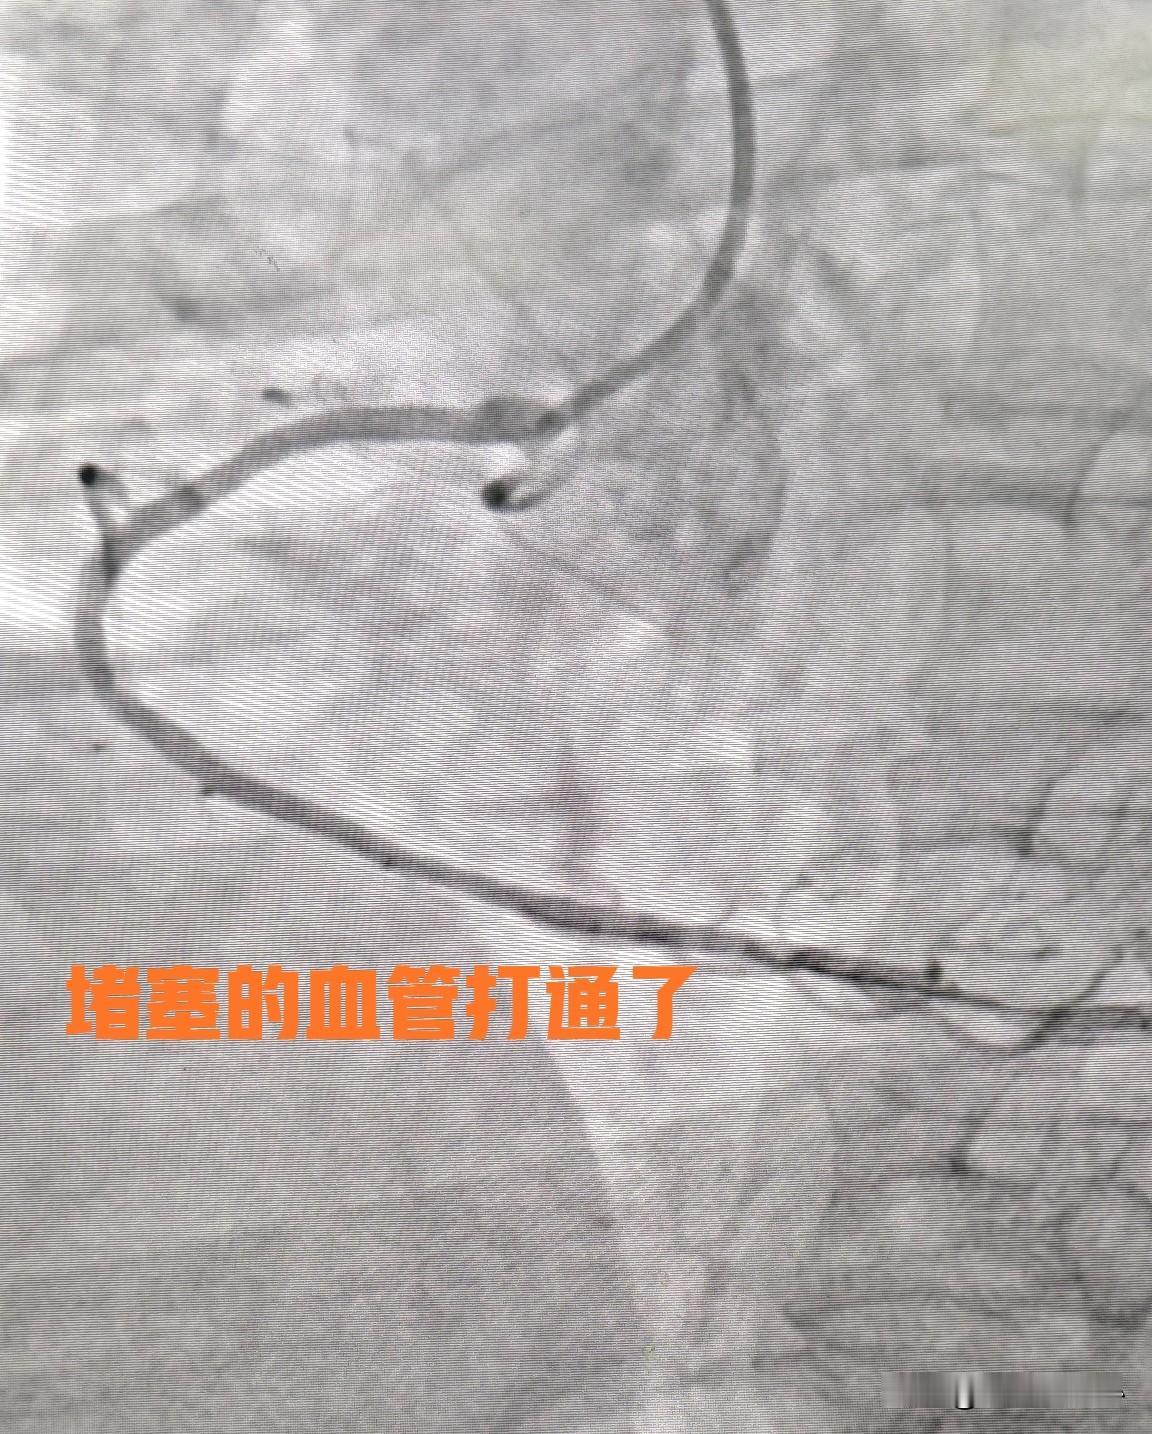

右冠脉闭塞打通了。71 岁男性患者,最近半年反复出现胸闷心慌的症状,尤其是日常活动以后,或者是吃的太饱以后就会出现,以前有高血压和糖尿病的病史。 从症状上看,很像冠心病的症状。但最终的确诊还是要靠冠状动脉CT或者冠状动脉造影。患者先到医院做了冠状动脉CTA,结果发现右冠状动脉重度狭窄。后来又做了冠状动脉造影。 结果发现右冠状动脉闭塞,完全堵住了,血流无法通过。开通有一定难度,算全力以赴,也有一部分患者无法打通。患者,一度心灰意冷,不想再做。最后经过家属的鼓励走上手术台。 最终经过两个多小时的鏖战,成功打通了血管。患者很开心,开始的坚持也有了意义。祝福他早日康复出院。心血管堵塞征兆